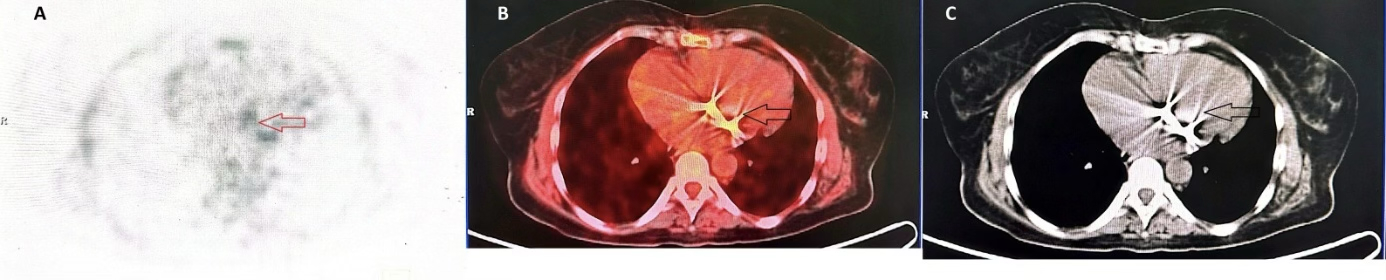

Case report: This report describes a 54-year-old female patient who underwent mitral valve replacement in 2018 for symptomatic severe mitral stenosis with atrial fibrillation. She presented with infectious symptoms on clinical examination. Following transthoracic and transesophageal echocardiography, the differential diagnosis included prosthetic valve infective endocarditis versus mechanical prosthesis thrombosis. [18F] FDG PET/CT ultimately confirmed the diagnosis of prosthetic valve infective endocarditis.

Conclusion: This case highlights the significant advantages of [18F] FDG PET/CT in the diagnostic evaluation of patients with suspected prosthetic valve infective endocarditis, particularly when conventional echocardiographic examinations are inconclusive.